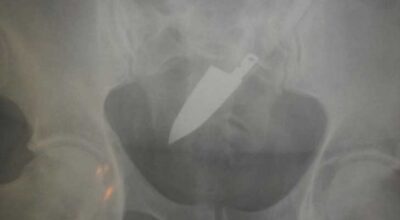

Esta recopilación de imágenes recoge alguna de las situaciones más estrambóticas que se han podido dar en una sala de rayos X. Todas ellas tienen algo en común: Son objetos extraños para el cuerpo humano que, de alguna manera han encontrado una vía de entrada, pero se han perdido a la hora de encontrar la de salida.

Muñecas de juguete descabezadas, botellas, armas, frascos, botes de plástico, teléfonos y hasta una cinta de casete pueden encontrarse en esa suerte de “punto limpio” al que ha quedado reducido el interior de los afectados.